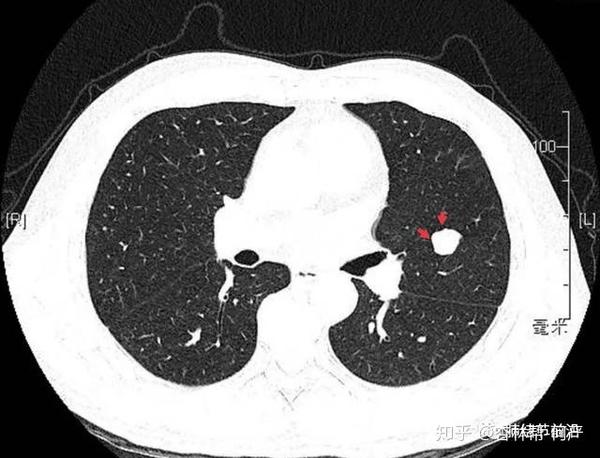

小细胞癌的肺结节形态

小细胞癌的肺结节形态,小细胞肺癌结节特点

体检发现右肺结节小细胞肺癌

小细胞肺癌结节特点

小细胞肺癌CT